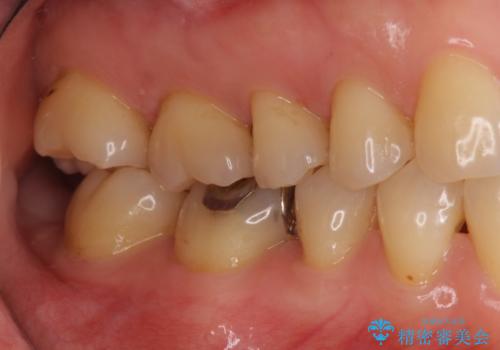

銀歯を白く セラミックインレーに

- 銀歯にしたのが20年以上前とのことで、白くやりかえたいということでした。

セラミックインレーにしています。

- 7万円(左下6 emaxプレスインレー 7万円)費用は治療当時の料金となります

銀歯を外して、下に虫歯があればしっかり取ります。しみるなどの症状が出る前がおすすめです。